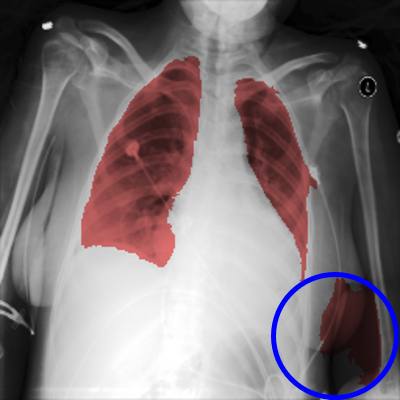

When applying a segmentation network, multiple regions may be returned as detected lung areas from each image. To complement the CBB, SA/LLA (Ratio of the smallest detected area to the largest detected area) and LA/LLA (Ratio of the second-largest detected area to the largest detected area) are used to evaluate lung lobe detection. Ideally, a reliable automated lung segmentation approach must find two complete lung lobes (i.e., two regions). In this case, (LA/LLA) and (SA/LLA) will be identical. Fig. 5 illustrates (LA/LLA) as a function of (SA/LLA). Commonly for both methods, the majority of observations follow an identity function, which means the algorithms mostly found two lung lobes per image. For those observations that did not follow the identity function, the two methods behaved differently. The difference is mainly rooted in two scenarios. Fig. 6 shows an example of a detected lung region by the two networks in the same image. In challenging CXR images, the methods may find more than one region per lung lobe (XLSor, Fig. 6-b). In this scenario, the segmented area does not have a significant effect on the final boundary box. However, in the second scenario, the algorithm mistakenly selects another area excluding the lung lobes (e.g., other parts of the body or background) as part of the lung area (UNB, Fig. 6-a). In this scenario, the final bounding box may cover a larger area than the lung region. Although the segmentation approach would not cause any loss of information for the second scenario, it questions the main purpose of lung segmentation (i.e., removing irrelevant regions and accurate localization of the lung area). As illustrated in Fig. 5, while XLSor mostly followed the first scenario, UNB followed the second one. Therefore, XLSor is a better segmentation network than UNB.

Refer to caption

Fig.6: Example of detected lung region by the two networks in the same image (a: UNB, b: XLSor).